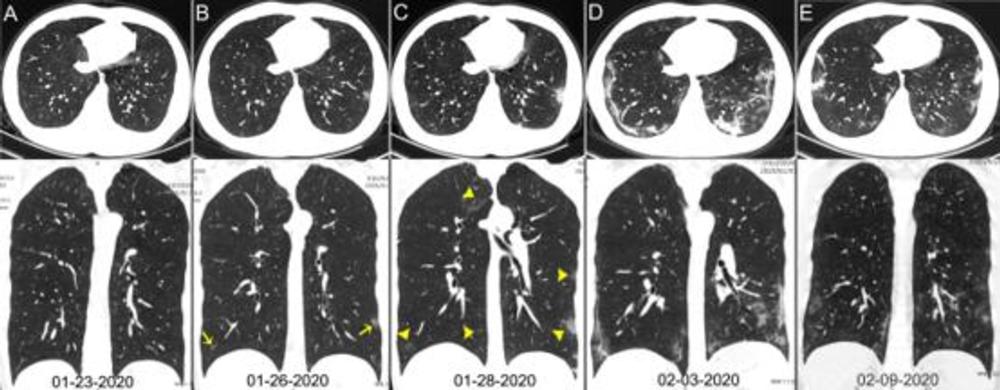

Figure 2. Chest CT images of a 29-year-old man with fever for 6 days. RT-PCR assay for the SARS-CoV-2 using a swab sample was performed on February 5, 2020, with a positive result. (A) Normal chest CT with axial and coronal planes was obtained at the onset. (B) Chest CT with axial and coronal planes shows minimal ground-glass opacities in the bilateral lower lung lobes (yellow arrows). (C) Chest CT with axial and coronal planes shows increased ground-glass opacities (yellow arrowheads). (D) Chest CT with axial and coronal planes shows the progression of pneumonia with mixed ground-glass opacities and linear opacities in the subpleural area. (E) Chest CT with axial and coronal planes shows the absorption of both ground-glass opacities and organizing pneumonia.